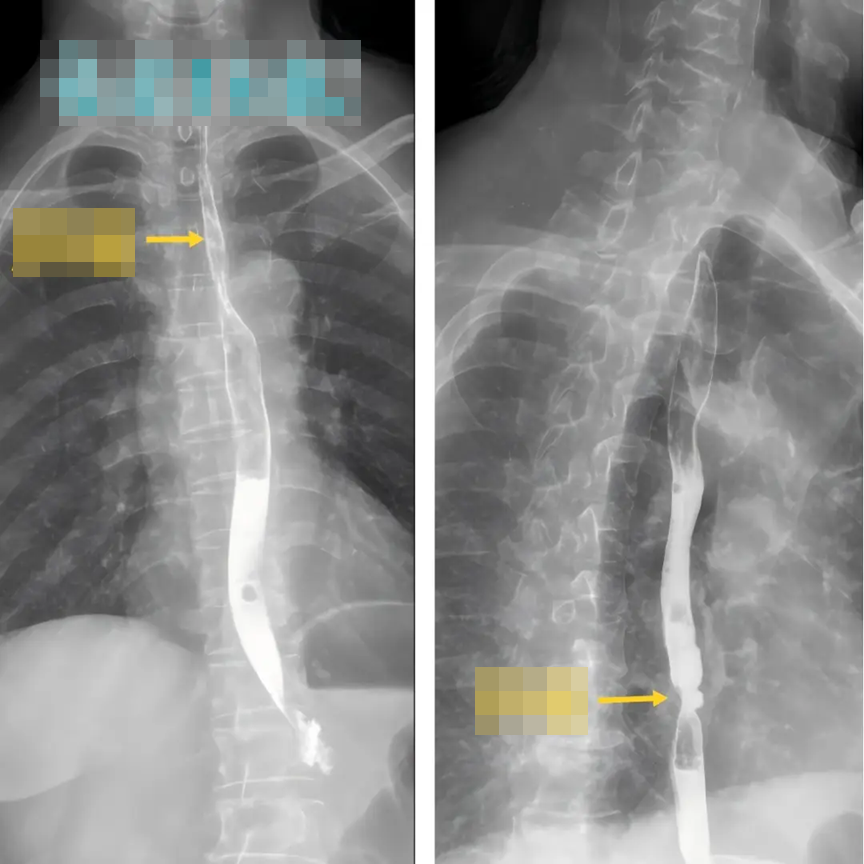

Tháng 1 năm nay, ông Từ (56 tuổi, sống tại thành phố Tuyền Châu, tỉnh Phúc Kiến, Trung Quốc) cùng vợ đi kiểm tra sức khỏe định kỳ tại bệnh viện địa phương. Kết quả nội soi dạ dày - thực quản khiến cả hai sốc nặng: cả hai đều được chẩn đoán mắc ung thư thực quản. May mắn là bệnh được phát hiện sớm, chưa có dấu hiệu di căn.

Sau khi đánh giá tình trạng bệnh, các bác sĩ đã chỉ định phẫu thuật nội soi trung thất để điều trị triệt căn ung thư thực quản cho cả hai bệnh nhân. Chỉ 5 ngày sau mổ, hai vợ chồng đã có thể xuất viện, sau khoảng một tuần phục hồi đã rút ống nuôi ăn và dần trở lại chế độ ăn bình thường.